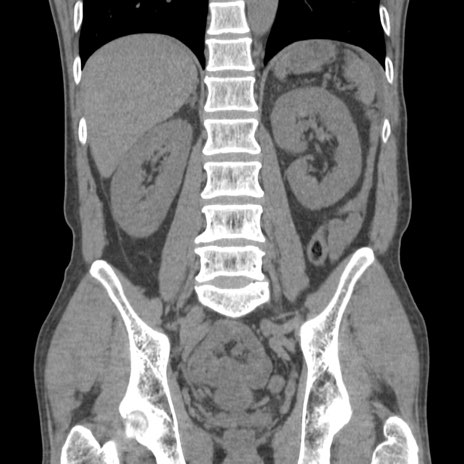

症例56 CT(冠状断像)

横断像